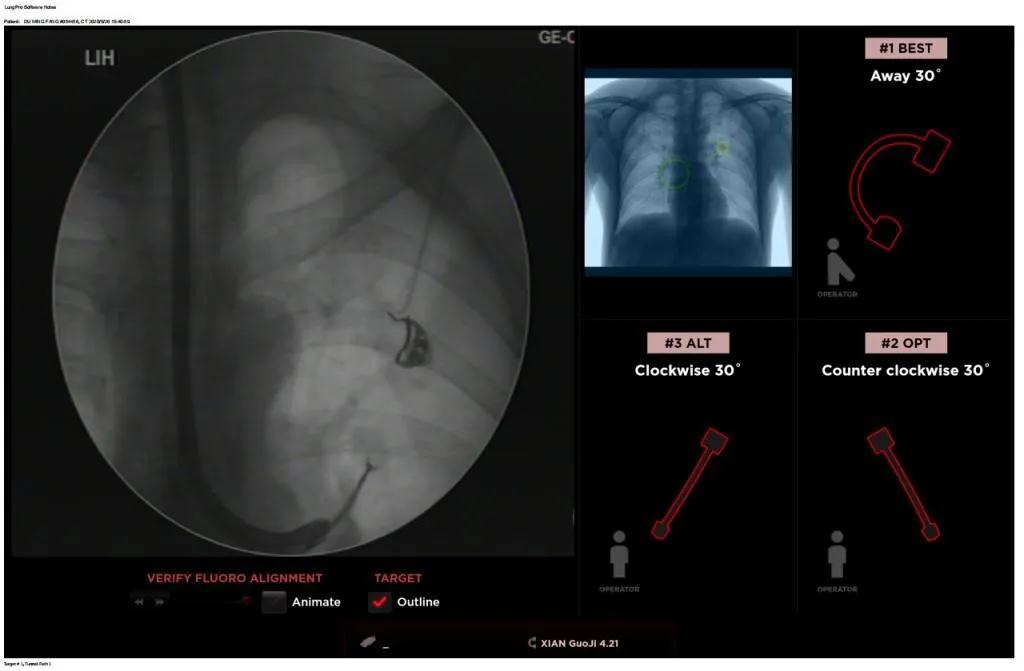

西安國際醫(yī)學(xué)中心醫(yī)院呼吸內(nèi)科完成西北地區(qū)首例LungPro全肺導(dǎo)航系統(tǒng)引導(dǎo)下BTPNA手術(shù)

近日,西安國際醫(yī)學(xué)中心醫(yī)院胸科醫(yī)院歐陽海峰副院長完成西北地區(qū)首例LungPro全肺導(dǎo)航系統(tǒng)引導(dǎo)下經(jīng)支氣管鏡跨肺實質(zhì)肺外周結(jié)節(jié)活檢術(shù)。

患者是一位59歲的男性,入院診斷左固有上葉前段肺小結(jié)節(jié),大小1.5cm*1.5cm。因為病灶與支氣管不相通,無法開展經(jīng)支氣管自然腔道的活檢,而且病變距離胸壁較遠(yuǎn)、肋骨阻隔進(jìn)針線路、病灶周圍有血管包繞,如果進(jìn)行CT引導(dǎo)下經(jīng)皮肺穿刺活檢,則存在較大的氣胸、出血等并發(fā)癥的風(fēng)險。

經(jīng)過充分的討論后,歐陽海峰副院長決定為患者實施LungPro全肺導(dǎo)航系統(tǒng)引導(dǎo)的經(jīng)支氣管跨肺實質(zhì)肺外周結(jié)節(jié)活檢術(shù)。Broncus導(dǎo)航系統(tǒng)LungPro具有全球領(lǐng)先獨(dú)創(chuàng)的BTPNA技術(shù)(支氣管鏡下跨結(jié)節(jié)抵達(dá)術(shù)),可以實現(xiàn)對氣道外周孤立性肺小結(jié)節(jié)的精準(zhǔn)定位,建立直接通往氣道外病變部位的通道,以實現(xiàn)全肺的診斷及后續(xù)治療。這項技術(shù)不僅彌補(bǔ)了現(xiàn)有支氣管鏡技術(shù)由于受限于病變部位是否有氣道可通向以及無法準(zhǔn)確定位病變部位而造成的較低診斷率,同時還彌補(bǔ)了CT引導(dǎo)下經(jīng)胸穿刺(TTNA)無法適用于某些特定部位如中央及肩胛骨等結(jié)節(jié)的問題,并且還避免了經(jīng)胸穿刺給患者帶來氣胸、出血的高風(fēng)險,可有效提高肺部結(jié)節(jié)及早期肺癌診斷陽性率,亦可用于早期肺癌的射頻消融或微波治療,具有微創(chuàng)、安全、同期雙肺診療等優(yōu)勢。

BTPNA技術(shù)整合了虛擬導(dǎo)航支氣管鏡VBN、氣道內(nèi)超聲rEBUS、TBNA、高壓球囊擴(kuò)張、X線輔助等多項三、四級呼吸內(nèi)鏡技術(shù)。歐陽海峰副院長有3000 TBNA、1000 rEBUS、500 VBN、800 球囊擴(kuò)張方面的技術(shù)積累,10年來個人每年完成三、四級呼吸內(nèi)鏡手術(shù)1200余例,這有效保障了BTPNA技術(shù)的順利開展。

團(tuán)隊術(shù)前進(jìn)行了精心的準(zhǔn)備,通過高分辨率CT建立了導(dǎo)航路徑,在麻醉科手術(shù)室的配合下,借助LungPro引導(dǎo)順利的確定了病灶部位、建立隧道并實施活檢,術(shù)后患者恢復(fù)順利出院。